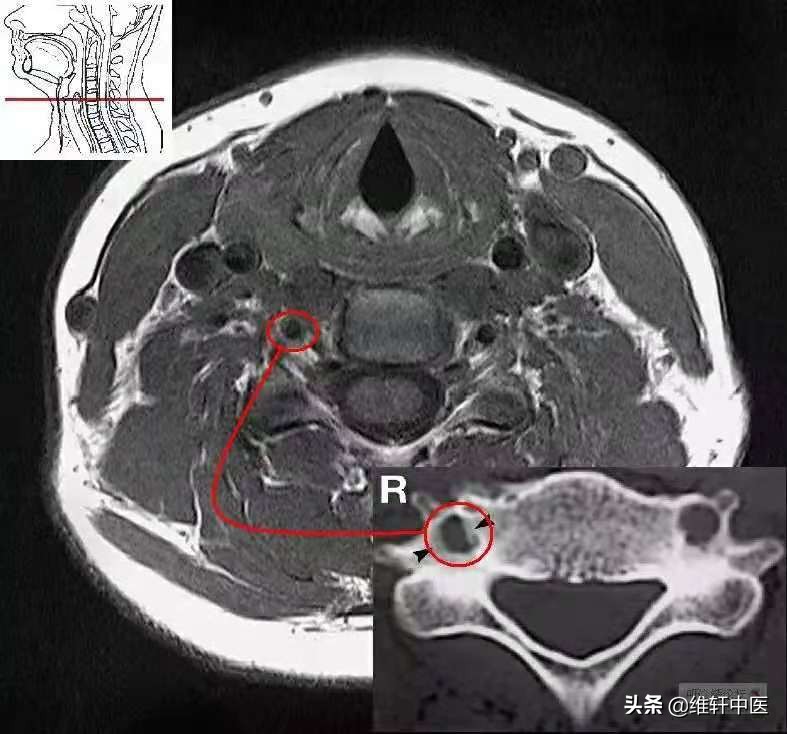

C5水平,横突孔狭窄,来自文献